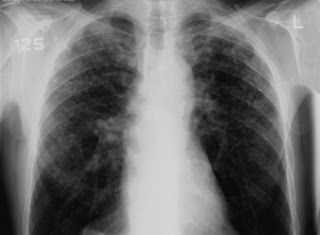

The cloudy spots on an undated chest X-ray shows the effects of silicosis on a gold miner. In 2011, South Africa said gold miners with silicosis could sue for compensation, and thousands plan to do just that